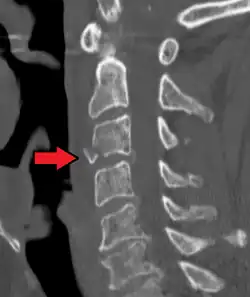

On CT scan or X-ray, a cervical fracture may be directly visualized. In addition, indirect signs of injury by the vertebral column are incongruities of the vertebral lines,[7] and/or increased thickness of the prevertebral space:[8]

![CT scan of normal congruous vertebral lines[7]](./_assets_/Vertebral_lines.png)